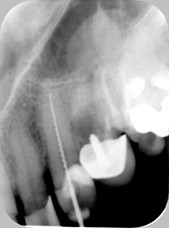

Jeżeli na przedstawionym poniżej zdjęciu długość części pracującej narzędzia kanałowego, które zostało wyprodukowane zgodnie ze standardem ISO i nie uległo wcześniej zniszczeniu, wynosi 13 mm to można stwierdzić że:

Pytanie 42